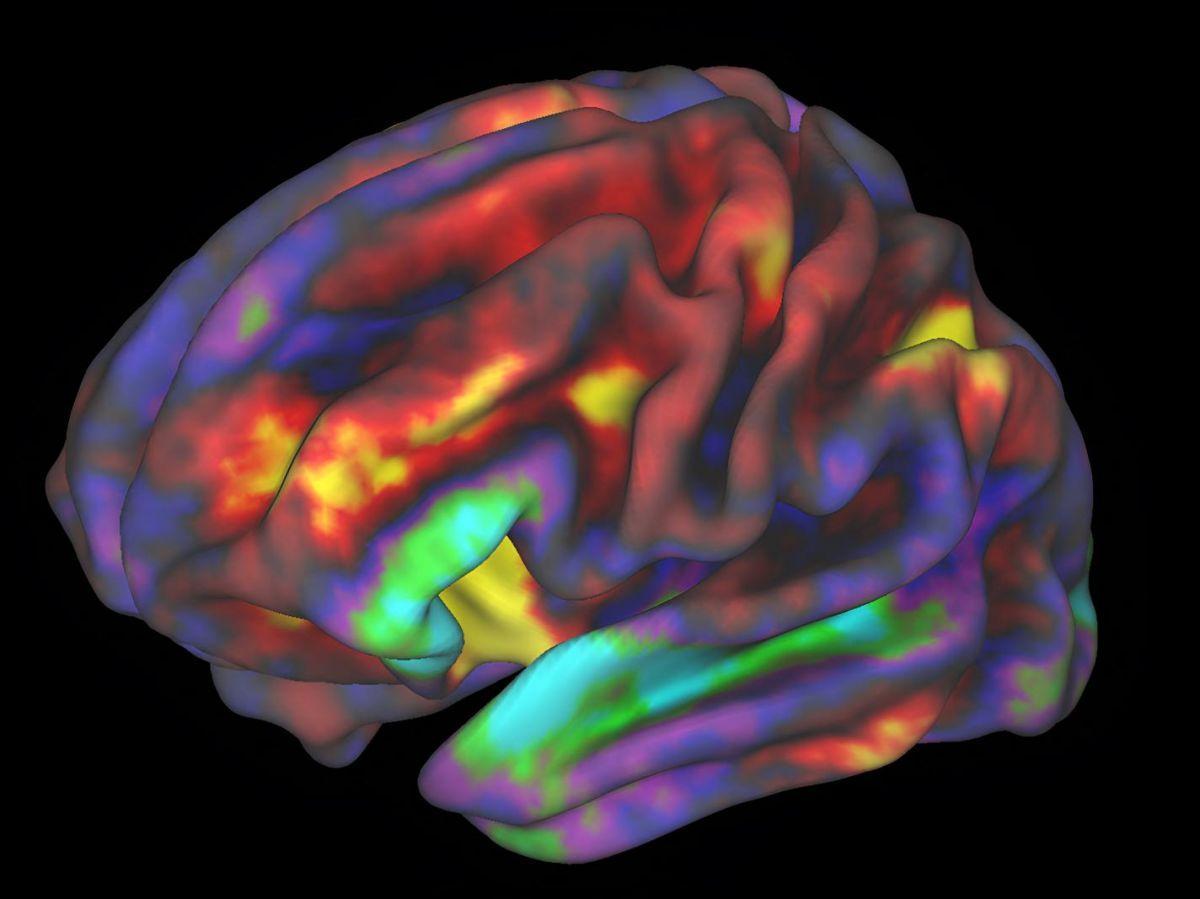

En parallèle, l’utilisateur regarde cette même séquence d’images et l’activité de son cerveau est enregistrée par IRM fonctionnelle (IRMf), qui permet d’analyser le flux sanguin dans le cerveau et ainsi savoir quelles aires sont activées en temps réel. Le but étant d’entrainer le système pour associer cette activité cérébrale aux traits sémantiques liés aux images observées. Pour ensuite pouvoir inférer les images que l’utilisateur observe ou imagine à partir des traits sémantiques associés à son activité cérébrale.

Deux expériences permettent de l’affirmer: d’abord, pendant la période de préparation, lorsque les participants sont devant l’écran et se préparent à regarder la vidéo, ils pouvaient lire le texte de description générée en amont par l’IA décrivant la vidéo. Pourtant, l’activité cérébrale enregistrée à ce moment produisait des descriptions beaucoup moins précises que lorsqu’ils regardaient la vidéo. Deuxièmement, l’analyse des seules régions cérébrales dédiées au langage ne produisait pas de descriptions aussi détaillées que l’analyse de l’ensemble du cerveau, y compris des régions cruciales pour le traitement des informations visuelles. Autrement dit, ce sont principalement les images recréées dans l’esprit qui permettaient de produire de bonnes descriptions.